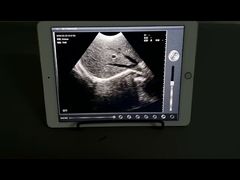

Kalite Portatif Ultrason tarayıcı, taşınabilir ultrason tarayıcı manufacturer from China